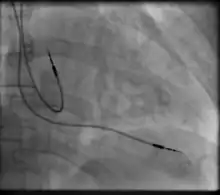

Right atrial and right ventricular leads as visualized under x-ray during a pacemaker implant procedure. The atrial lead is the curved one making a U shape in the upper left part of the figure.